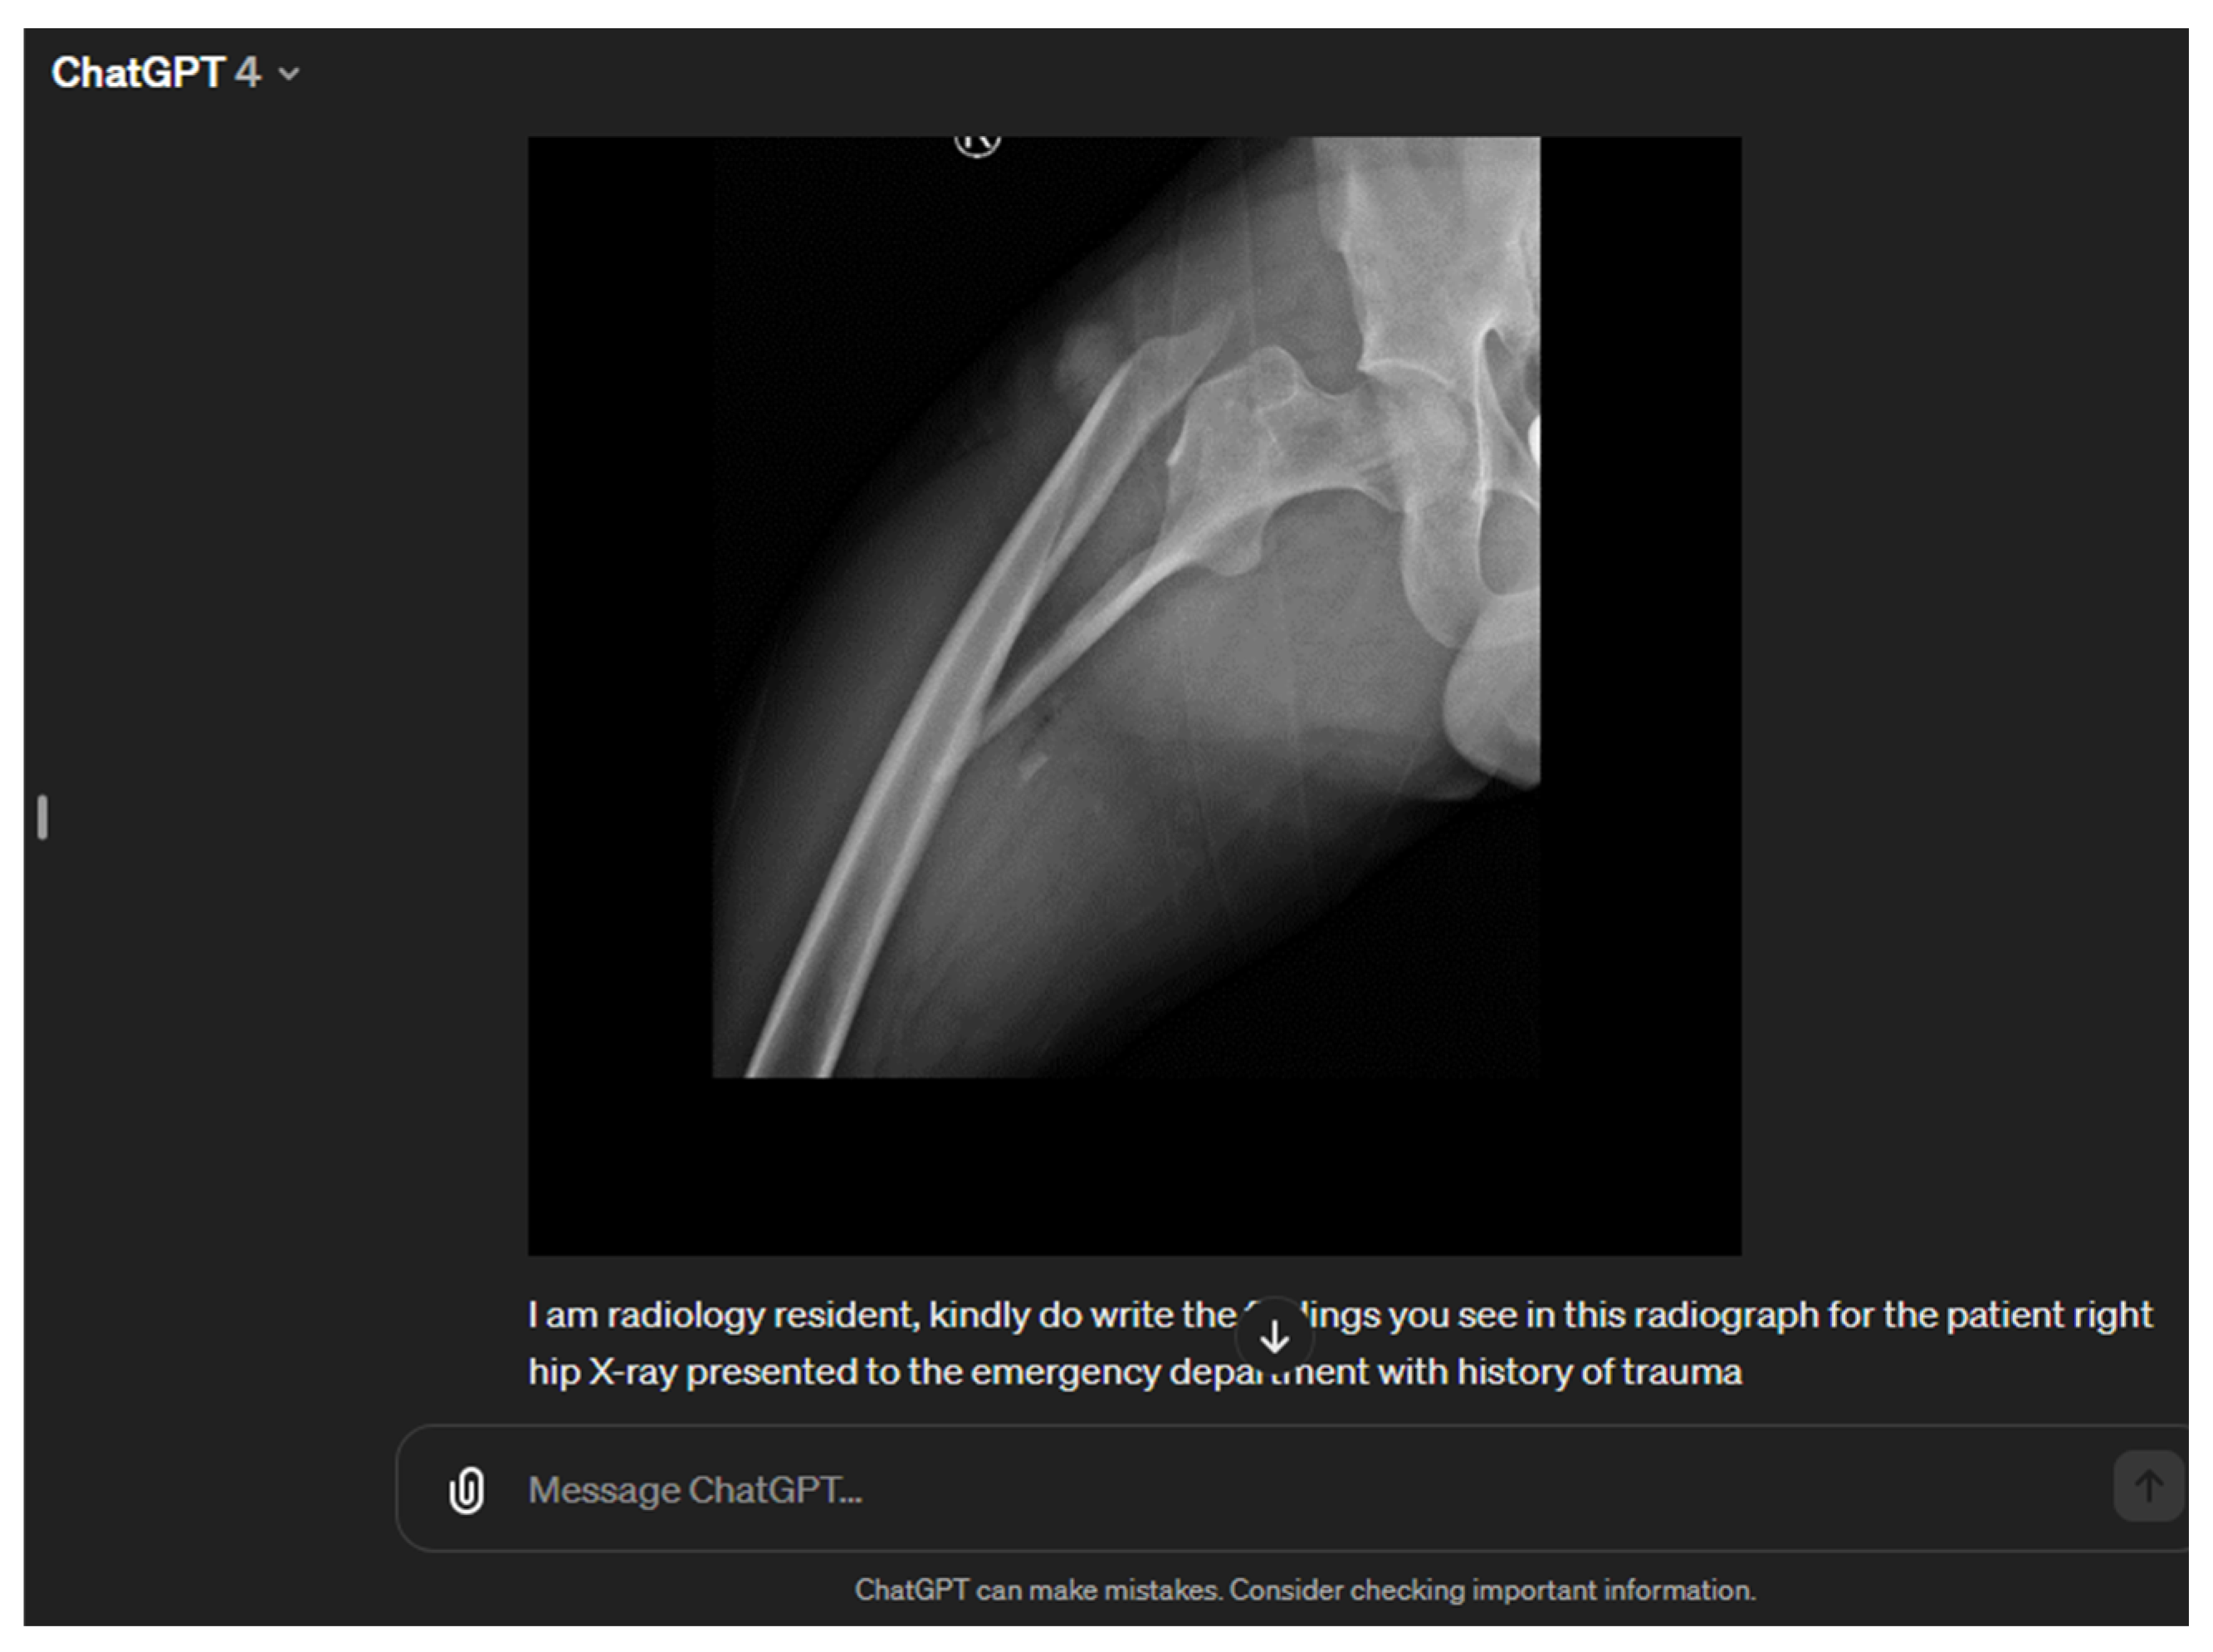

Role of ChatGPT-4 in Musculoskeletal Imaging